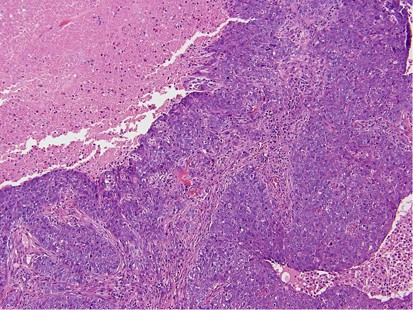

Immunohistochemistry was used in the initial work-up of 38 (45%, 38/85) cases. In all of these cases, the primary tumors were known, except for one case in which a patient had a choriocarcinoma that had yet to be detected. Melanoma was the most frequent tumor stained (9/85), followed by lung (6/85). The most frequently used antibodies included ER, PR, AE1:AE3, S100, and TTF-1. Diagnostic errors occurred in 10 cases (12%, 10/85), the majority of these being ovarian high-grade serous carcinoma (60%, 6/10) (Figure 3). In three of the patients with ovarian cancer who were misdiagnosed as a primary breast carcinoma, the biopsy was initially misinterpreted at an outside institution. After a full clinical work-up was performed at MSKCC, the ovarian primaries were discovered and this information was then communicated to the pathologist and the diagnoses were subsequently amended. In the cases of the remaining three patients with ovarian cancer, the patients were initially treated at another institution and the history of the ovarian primaries was not immediately available. After this history was revealed, the previous material was obtained and compared to the breast/axillary lesion, resulting in a correct diagnosis. The patients with melanoma and lung primaries were misdiagnosed, again, due to the failure of the clinician to communicate the history of a prior malignancy. After this information was relayed to the pathologist, the diagnoses were subsequently changed. In the remaining two cases, the primary tumors, medullary thyroid carcinoma (Figure 4) and hepatic carcinoid tumor (Figure 5) had yet to be discovered. After a full clinical work-up, the thyroid and liver lesions were found and compared to the metastatic tumors. In addition, immunohistochemical stains were performed on the metastases, which helped to render the correct diagnoses.

High-grade ovarian serous carcinoma metastatic to the breast. The tumor has overlapping morphologic features with primary breast cancer with medullary or atypical medullary features including a solid growth pattern, central necrosis, a host inflammatory response and marked cytologic atypia. Ovarian high-grade serous carcinoma was the most commonly misdiagnosed tumor in this series.

In this series, ovary was the most common primary site among all of the carcinomas. In keeping with other reported series,7, 8, 9 our study found that high-grade serous carcinoma was the most frequent ovarian carcinoma type to metastasize to the breast or axilla. This tumor was also the type most often misdiagnosed initially due to overlapping morphologic and immunohistochemical features with a primary breast cancer. Both tumor types can have a wide range of histologic appearances, including papillary, glandular, and solid architecture with necrosis and high-grade cytology; it can be extremely difficult to differentiate the two without knowledge of a prior ovarian primary. In some instances, even when a primary ovarian carcinoma is known, it may still be a diagnostic challenge morphologically. Immunohistochemical studies can be helpful in problematic cases. ER and PR are frequently expressed in both breast and ovarian carcinomas and are therefore of limited value. PAX8, on the other hand, has been shown to be positive in nearly all gynecologic cancers and, to date, is negative in breast cancers.10, 11 In one study of PAX8 expression in ovarian and breast carcinoma, the marker was immunoreactive in 87% (108/124) of the ovarian carcinomas studied. The ovarian tumors positive for PAX8 included serous, endometrioid, and clear cell, while mucinous carcinoma was usually negative. If ovarian mucinous carcinomas were excluded, PAX8 was positive in 96% of the primary ovarian carcinomas. None of the 243 cases of breast carcinoma studied were found to be PAX8 positive.11 WT1 is another marker that may be useful in this setting. It has been shown to be a rather sensitive marker in ovarian serous carcinoma as it is positive in up to 85% of the cases,12 while rarely positive in breast cancer (2.1% in one report).11 There are a few exceptions, however. Domfeh et al13 found WT1 expression in 64% (21/33) of pure and 33% (11/33) of mixed mucinous breast carcinomas with either ductal (no special type) or micropapillary components; however, the WT1 staining was usually weak and focal in most of the positive breast tumors.

In this series, the failure of the pathologist to recognize the metastatic nature of the lesion resulted most often because of the absence of a prior cancer history provided by the clinician at the time of initial interpretation. Six of these tumors were high-grade serous carcinoma and were misdiagnosed because of the overlapping morphological and immunohistochemical features as described previously. The other tumors (lung adenocarcinoma, liver carcinoid, medullary thyroid carcinoma, and melanoma) all had appearances that may be compatible with a primary breast cancer. Tumors that appear to be relatively well-differentiated, however, would be expected to express estrogen and progesterone receptors if they were indeed primary mammary carcinomas. Such a finding should prompt the pathologist to investigate the clinical history more thoroughly in order to rule out or suggest the possibility of a metastatic lesion. Compounding the problem is the observation in our study that 75% of metastases presented as solitary lesions, as opposed to multiple metastatic lesions commonly observed in other organs such as liver and lung. The implementation of electronic medical records in our institution has allowed the pathologist easy access to the patient’s history. Despite this, our clinicians are urged to always provide a complete history, as records and procedures from outside institutions are not always immediately available.